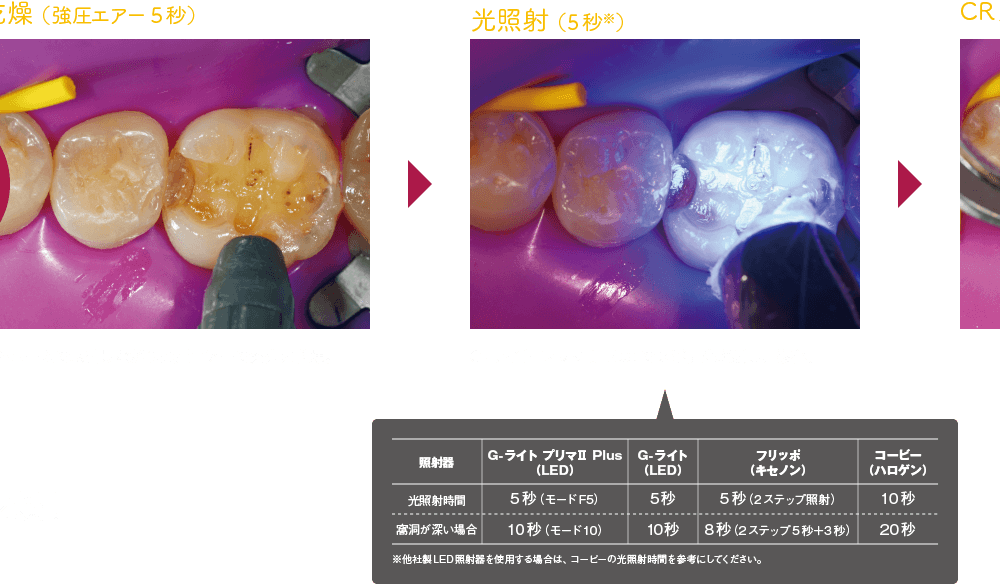

基本ステップ(コンポジットレジン修復)